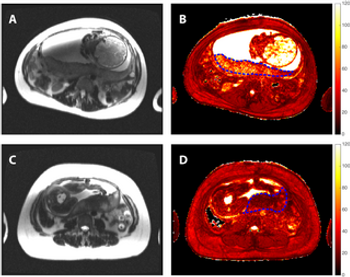

Noting that the machine learning model incorporating magnetic resonance imaging (MRI) had a higher mean area under the curve (AUC) than a model based solely on clinical features for predicting hepatocellular carcinoma recurrence, researchers said the study findings could have implications for refining liver transplant criteria.